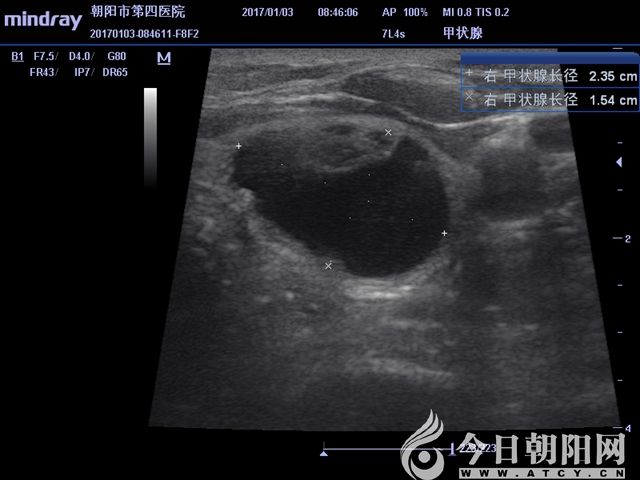

超聲測得實性結節(jié)大小

患者為65歲女性,發(fā)現(xiàn)左右側頸部包塊1個月,通過超聲檢查考慮甲狀腺腺瘤伴出血。患者從心理上不能接受頸部手術后切口瘢痕,拒絕手術切除,要求微創(chuàng)治療。針對患者要求,該院外科團隊為其設計了治療方案——行甲狀腺微波消融術。手術采用局麻,在超聲影像引導下,順利準確穿刺,抽出積血后,再于實性病變處用活檢針穿刺取病理,證實良性病變。